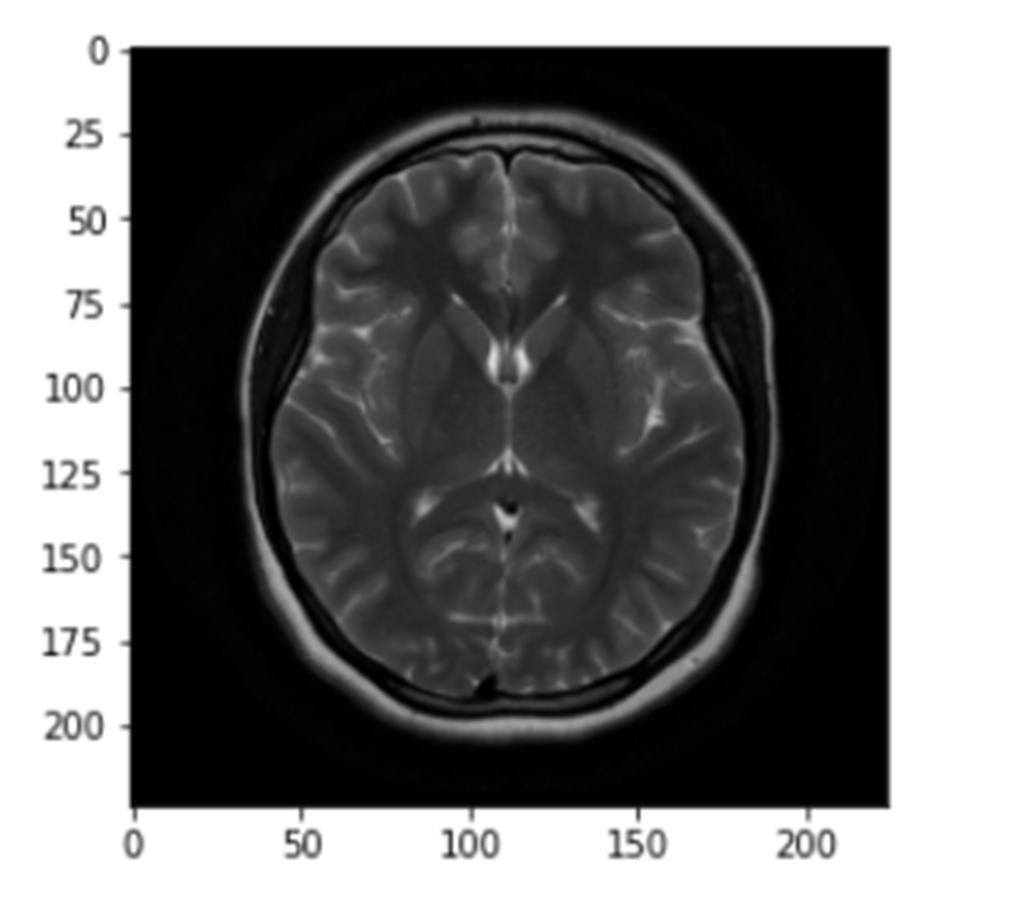

Several methods of detecting tumors in concatenated MRI images were analyzed and applied to the dataset available on the Kaggle website, the images were divided into two groups: with and without tumors, based on which we used various deep learning and machine learning methods and VGG16 model.

Fig 1. Dataset Images